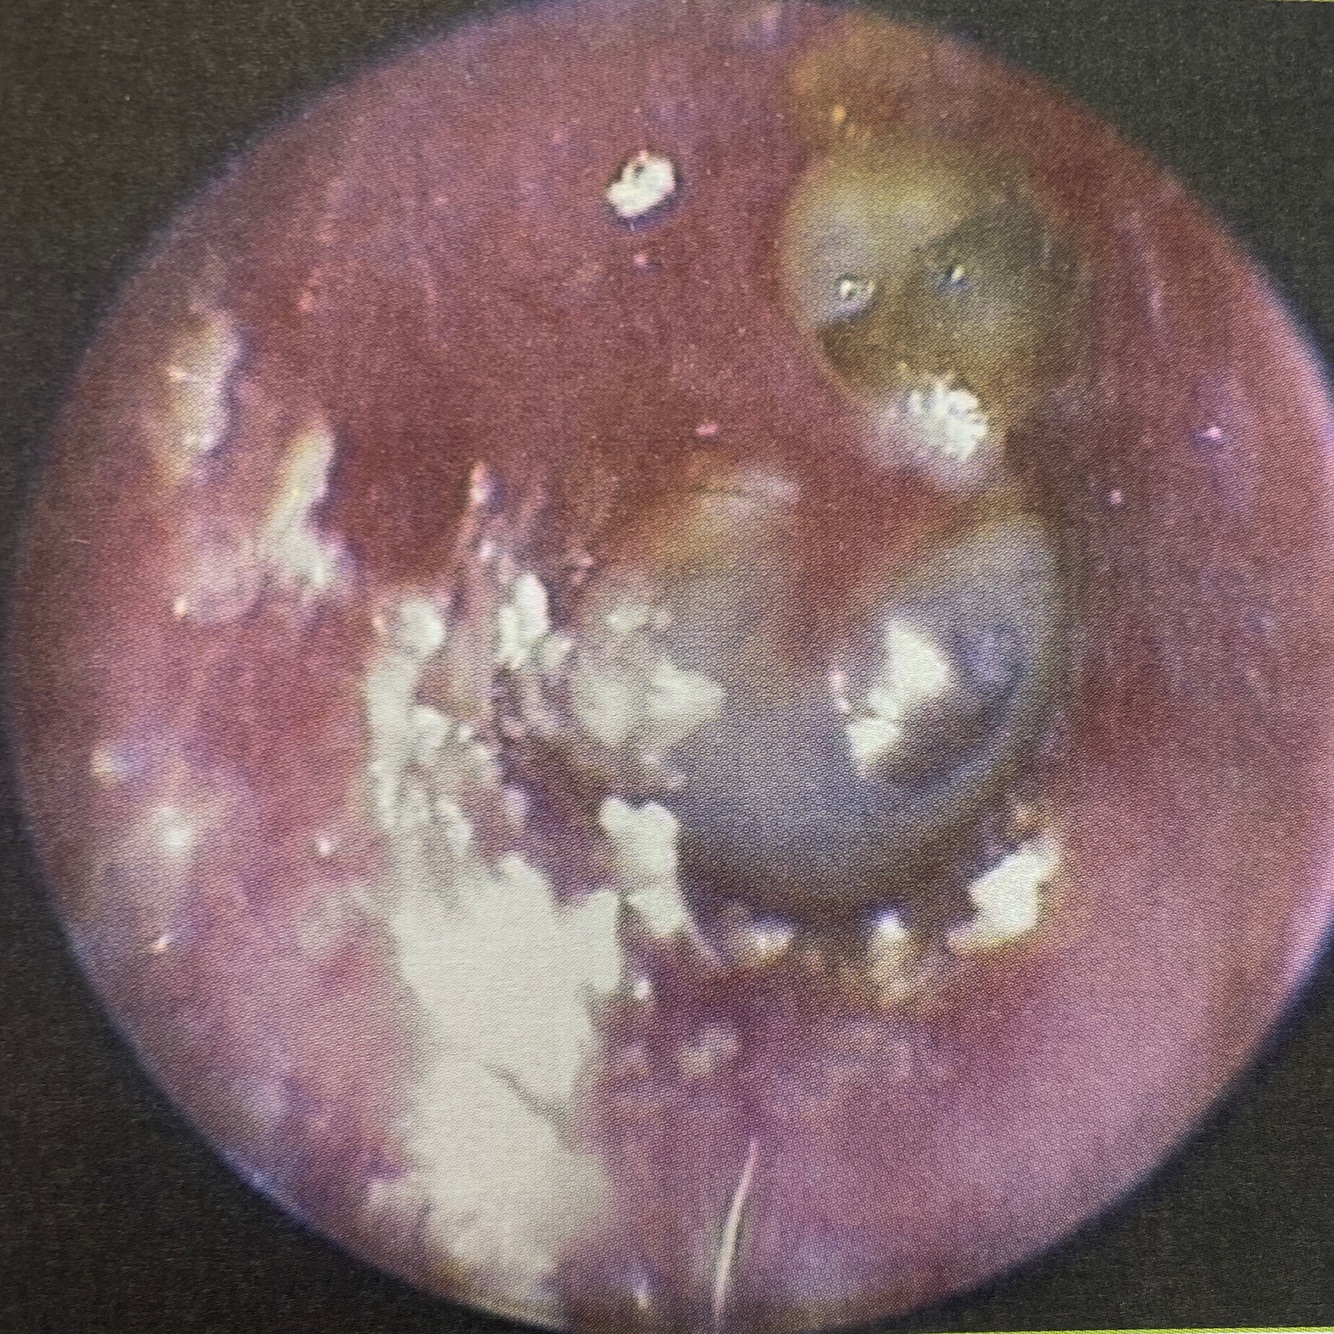

A

Colesteatoma oido

( Epitelio queritinizante en oido medio con sustancias que producen osteólisis en oído medio )